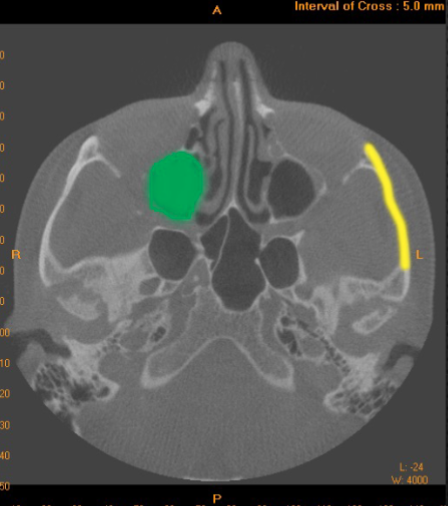

zygomatic process

identify the structure

zygomatic arch

what is indicated by the YELLOW

maxillary sinus

what is indicated by the GREEN dot